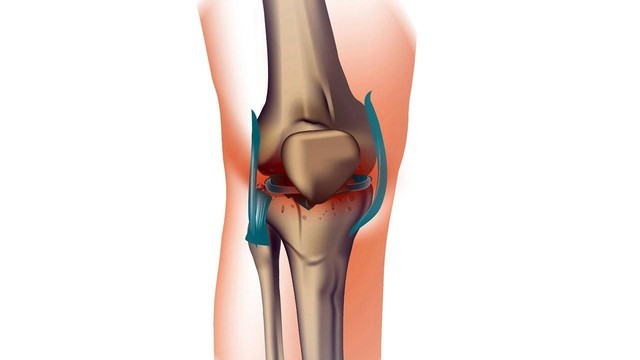

Симптомы

Деформирующий артроз может поразить любой сустав. Однако наиболее подвержены артрозу тазобедренный, коленный и локтевой. Повышенный риск развития недуга в этих сочленениях связан с тем, что именно они испытывают наибольшую нагрузку в повседневной жизни. Артроз проявляется в виде болей, которые сначала носят слабовыраженный характер. С прогрессированием недуга они становятся все сильнее. Провоцируют их различные физические нагрузки. В острой стадии заболевания боли не прекращаются после продолжительно отдыха и могут мучить человека даже в состоянии покоя. Помимо этого, к симптомам можно отнести скованность в суставах и специфический хруст во время движения.

Этапы заболевания

Деформирующий артроз развивается стадийно. Специалисты выделяют три основных этапа развития заболевания. Недуг на первой стадии развития не приносит человеку сильных беспокойств. Это начальный этап, при котором неприятные ощущения в суставах могут возникать достаточно редко, только после интенсивных физических нагрузок. Никаких структурных изменений при этом еще нет, однако устойчивость и выносливость уже значительно снизилась.

На втором этапе развития деформирующего артроза человек начинает ощущать следующие симптомы:

Третья стадия заболевания считается самой сложной. Она приносит сильнейшие боли, которые не прекращаются даже во время сна. На этом этапе развития недуга для больного каждое движение в суставе мучительно. Справиться с артрозом третьей стадии достаточно сложно, консервативные способы лечения обычно уже не оказывают эффекта, поэтому проводится операция по замене всего сустава или его частей.